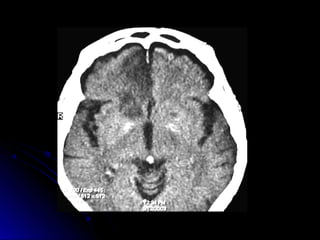

Ubicación de las lesiones en TAC-RNM

DIAGNOSTICO:DIAGNOSTICO: Laboratorio. hemograma, glucemia,ionograma, ESD, tiempo deQuick, KPTT, orinacompleta Evaluación neurológica Radiologíatórax frente ECG y Evaluación Cardiológica, Eco bidi, Doppler TAC cerebral RNM (utilidad técnicadedifusión y percusión) Eco Doppler VasosCuello,  Angio RNM, Arteriografía

Ubicación de laslesiones en TAC-RNM